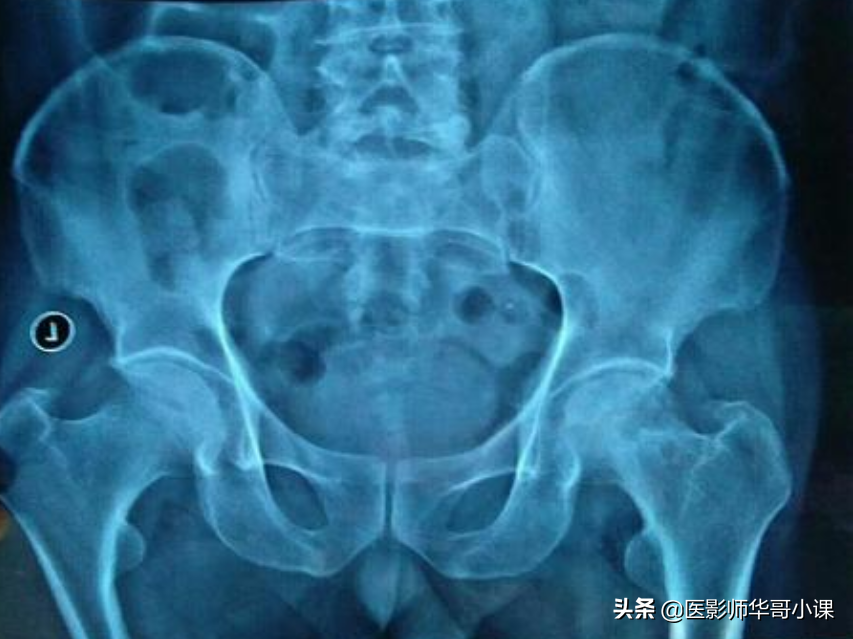

第六节大腿与髋

2.股骨颈偶可见环形阴影,为软骨岛。该影内可见重叠的松质骨结构,切勿误为病理变化,在正常的壮年人中,股骨远端背内侧壁皮质有局限性,对称性外壁增厚,也不可误认为病理情况。

3.股骨大小转子的化骨核可为多个,形态可不规则。

4.在股骨大转子外或上可有滑囊钙化,亦称腱鞘钙化。

5.在不标准的股骨近侧位片上,小转子可能和股骨干重叠形成三角形密度减低区,颇似骨破坏。

6.臀肌粗隆线在股骨侧位片上,股骨上段后面臀肌粗隆呈凹凸粗糙不整或较光滑,是臀大肌的附着点,为正常变异,不要误为骨膜增生。

7.小儿的髋关节诸骨,因软骨较厚,关节腔显得较宽,各骨间距离亦较远,所以有时很难肯定是否为髋关节脱臼,尤其在投照时,若两下肢的位置不对称,一侧稍外旋,股骨显得较短,可能误认为脱臼,Shenton氏线有助于鉴别。

8.2~4岁小儿的髋臼边缘高低不平,欠规则。10岁以后逐渐趋向整齐。在正位片上,14~18岁时髋臼外缘可能出现多余的化骨核,呈三角形或卵圆形,有时可分裂成3~4个小块,称髋臼小骨。

9.髂嵴在初生时是光滑的,2~3岁变为不规则,青春期出现二次化骨核,这些化骨核往往不整齐或呈分节状。

10.在髂骨翼部有时可找到放射状及“丫”形血管沟阴影。

11.肠内气泡和髂骨重叠,好象是骨质破坏。

12.髂角为发自髂骨翼向上向生突出的骨质隆起,为多种内胚层或外胚层发育缺陷之一。

13.骶髂关节骶侧的二次骨化中心,多于15~16岁出现,此时关节面略呈模糊并增宽,系正常变异,不要误为病变。

14.骶骨下切迹,骶骨下部一侧或两侧有局限性骨凹陷,深度不一,两侧往往不对称,很象骶骨肿瘤。

15.骶髂关节旁沟即解剖学上的耳前沟,位于小骨盆腔后缘,骶髂关节下方髂骨侧表现为半圆形或浅弧形切迹,为骶髂韧带附着处,也是女性骨盆特征之一,此切迹有时也可出现于骶髂关节的骶骨侧。

16.坐骨结节的二次化骨核有时不完整,呈分节状。

17.妇女的耻骨联合在生育前后增宽,可出现透亮裂隙,(潜在关节腔)其出现率达41.5%,偶可见于男性。